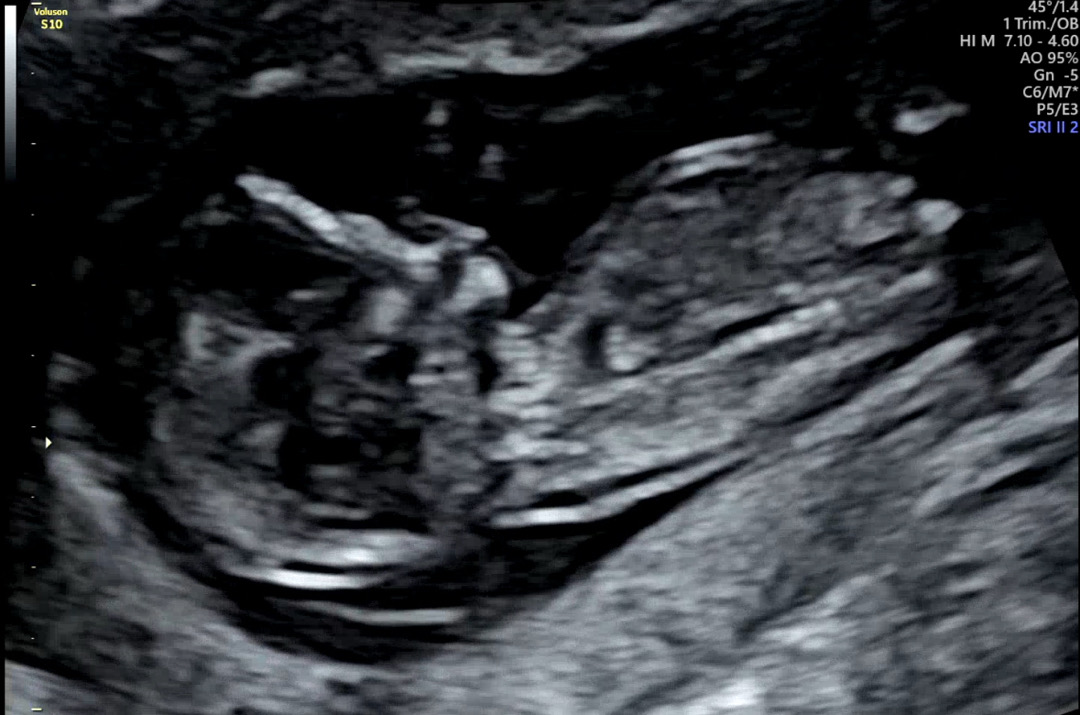

12주5일 됐는데 전 딸랑구 같은데 마미들이 보기엔 어떤가요??ㅎㅎ